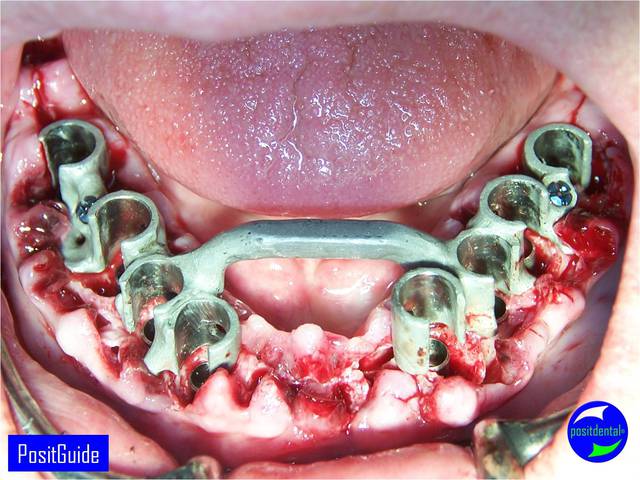

Mise en Charge Immédiate Post Extractionnelle , MCIPE partie chirurgicale de A à Z

implants in situ et S.I.A.O pré-opératoire